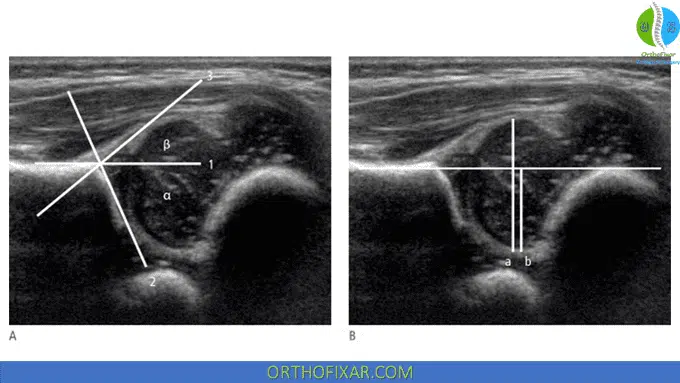

Alpha (α) and Beta (β) Angles:

All angles are measured in relation to the “baseline,” which is tangent to the lateral border of the ilium. Two more reference lines are drawn along the bony roof of the acetabulum (acetabular roof line) and along the acetabular labrum (labral line}:

- The acetabular roof line is drawn from the superior bony rim of the acetabulum to the lower edge of the ilium in the acetabular fossa.

- The labral line runs from the labrum to the superior bony rim of the acetabulum or to the transition point from the convexity of the superior bony rim to the concave acetabular roof.

The intersections of the acetabular roof line and the labral line form the alpha (α) and beta (β) angles of the hip:

- The α angle is formed by the baseline and acetabular roof line and reflects the bony coverage of the femoral head.

- The β angle, formed by the baseline and labral line, is a criterion for evaluating the cartilaginous acetabular roof.